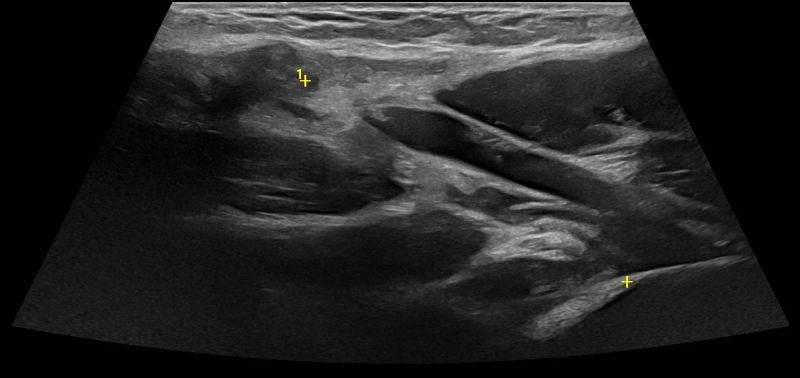

Elbow Ultrasound provides comprehensive imaging of various structures in the region, allowing the identification of pathologic conditions in the joint, bursae, tendons, ligaments, nerves, and soft tissues of the elbow.

Elbow Tendons

- Lateral Epicondylitis (Tennis Elbow)

- Medial Epicondylitis (Golfer’s Elbow)